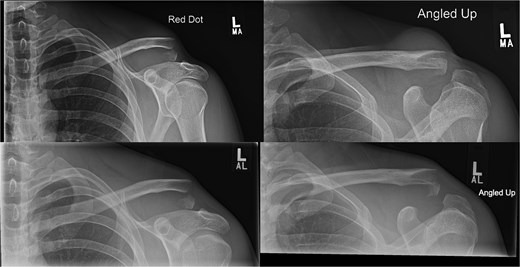

Radiographs of third case showing a displaced lateral clavicle fracture with deformity.

A 27-year-old male suffered a right lateral clavicle fracture after a fall (Fig. 5). He underwent TightRope fixation with stabilization of the coracoclavicular ligament. Rehabilitation was initiated early, and by three months, he had full shoulder motion and returned to overhead sports. Radiographs confirmed union, and the patient reported minor scar sensitivity and transient keloid formation, with no functional limitations (Fig. 6A–D).